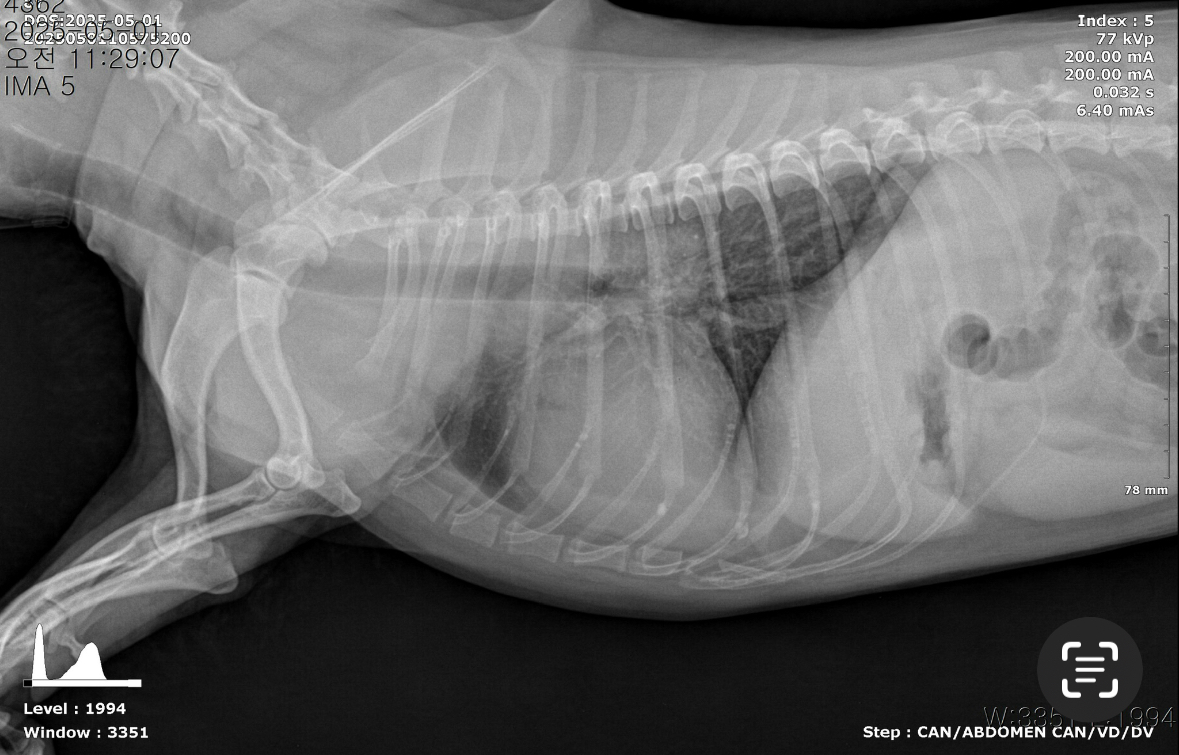

[엑스레이]